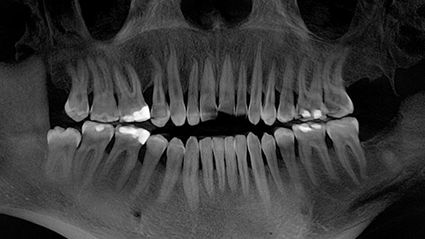

Im Januar 2019, vor sechs Monaten, hatte ich meine Kavitationsoperation in der Swiss Biohealth Clinic. Ich hatte Kavitationen an allen vier Weisheitszahnstellen. Die beiden linken Weisheitszähne waren 2008 raus. Die rechten waren noch da und mussten gezogen werden, um die Karies zu beseitigen.